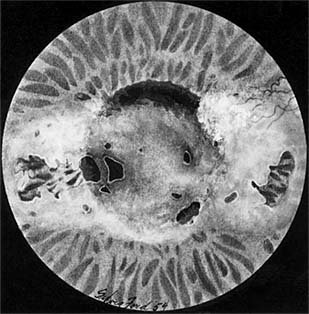

Blurred vision is the only symptom. Many patients present with rapidly increasing myopic astigmatism. Signs include cone-shaped cornea (Figure 6-11); linear narrow folds centrally in Descemet's membrane (Vogt's lines), which are pathognomonic; an iron ring around the base of the cone (Fleischer's ring); and, in extreme cases, indentation of the lower lid by the cornea when the patient looks down (Munson's sign). There is an irregular or scissor reflex on retinoscopy and a distorted corneal reflection with Placido's disk or the keratoscope-all of which often being more obvious in the early stages than the other corneal signs. Color-coded topography units provide more accurate information on the degree of corneal distortion (Figure 2-26). Generally, the fundi cannot be clearly seen because of corneal astigmatism.

Figure 6-11

Figure 6-11: Keratoconus.